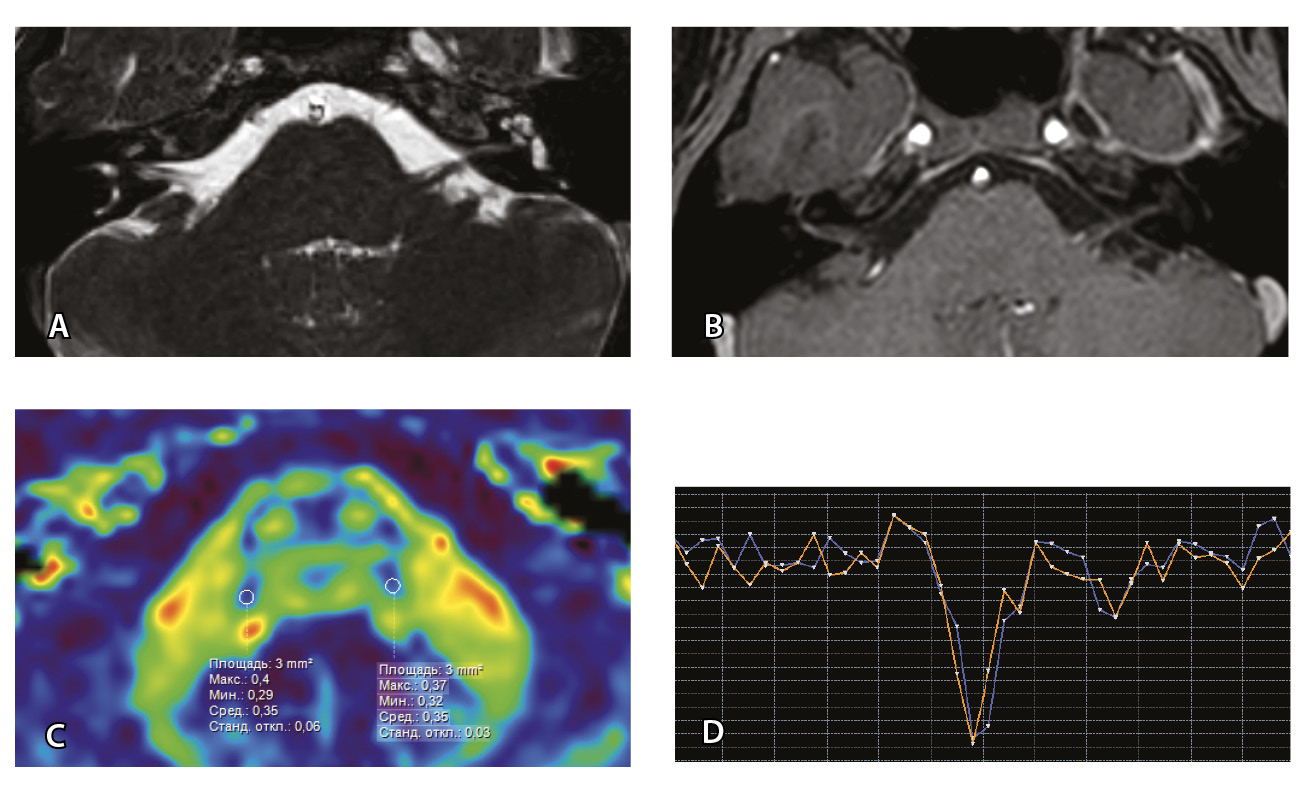

Далее представлены изображения МП-МРТ пациентов с НЛН и клинико-неврологическими данными, свидетельствующими в пользу ПБ. Для максимальной наглядности вышеуказанные клинические случаи (№ 2 и № 3) представлены в виде таблицы (рис. 7).

Рис. 7. Клиническое наблюдение 2, пациент 6 лет (А, Б, В, Г). Магнитно-резонансная томография (МРТ) головного мозга: А – прицельная T2-SSFP на область мосто-мозжечкового угла; Б – Т1-взвешенное изображение с контрастным усилением; В – диффузионно-тензорная МРТ (фракционная анизотропия, ФА); Г – Т2*-перфузия. На изображении T2-SSFP отмечается утолщение корешков лицевого, вестибуло-кохлеарного нервов во внутренних слуховых проходах (А, желтые стрелки) и интенсивное накопление ими контрастного вещества (Б, красные стрелки). На уровне моторных ядер лицевых нервов в заднем отделе варолиевого моста значения ФА симметричны (В), признаков гипо-/гиперперфузии не выявлено (Г).

Клиническое наблюдение 3, пациент 13 лет (Д, Е, Ж, З). МРТ головного мозга: Д – прицельная T2-SSFP на область мосто-мозжечкового угла; Е – Т1-взвешенное изображение с контрастным усилением; Ж – диффузионно-тензорная МРТ (ФА); З – Т2*-перфузия. На изображении T2-SSFP патологические изменения на уровне прохождения лицевых нервов во внутренних слуховых проходах не определяются (Д). В медиальном отделе правого полушария мозжечка определяется объемное образование, компримирующее стенку IV желудочка и задний отдел варолиевого моста без признаков васкуляризации (Е). На уровне моторных ядер лицевого нерва в заднем отделе варолиевого моста на изображениях ФА на стороне поражения отмечается минимальное уменьшение показателя ФА до 0,27 (Ж, черная стрелка) и признаки гипоперфузии (З, оранжевый график) по сравнению с контралатеральной стороной (З, синий график)

При этом в клиническом наблюдении № 2 из анамнеза жизни известен ранее установленный диагноз лимфобластного лейкоза в стадии ремиссии. В клиническом наблюдении № 3 значимых анамнестических сведений и данных в пользу атипичного течения ПБ получено не было.

Таким образом, при помощи информации, полученной при проведении МП-МРТ, в обоих случаях был установлен симптоматический характер НЛН, обусловленный развитием неопластических процессов. Оба пациента были направлены в профильные хирургические стационары для проведения дальнейшего лечения.